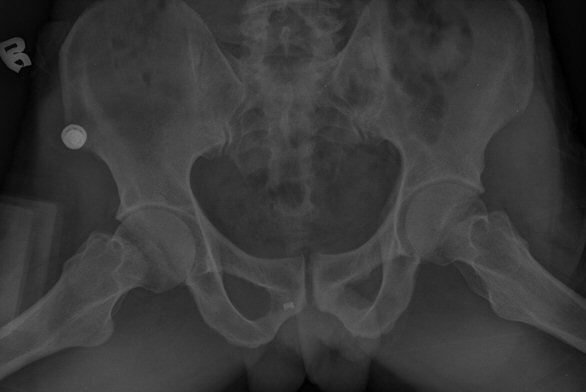

ÃÊÁø ½Ã ½ÃÇàÇÑ ¹æ»ç¼± ÃÔ¿µ»ó ÀüÇÏÀ屨 ºÎÀ§¿¡¼­ ¼®È¸È­ À½¿µÀÌ °üÂûµÇ°í, 3ÁÖ ÈÄ ½ÃÇàÇÑ ÃÔ¿µ¿¡¼­

¼®È¸È­ À½¿µ ¼Ò½ÇÀÌ È®ÀεÊ.